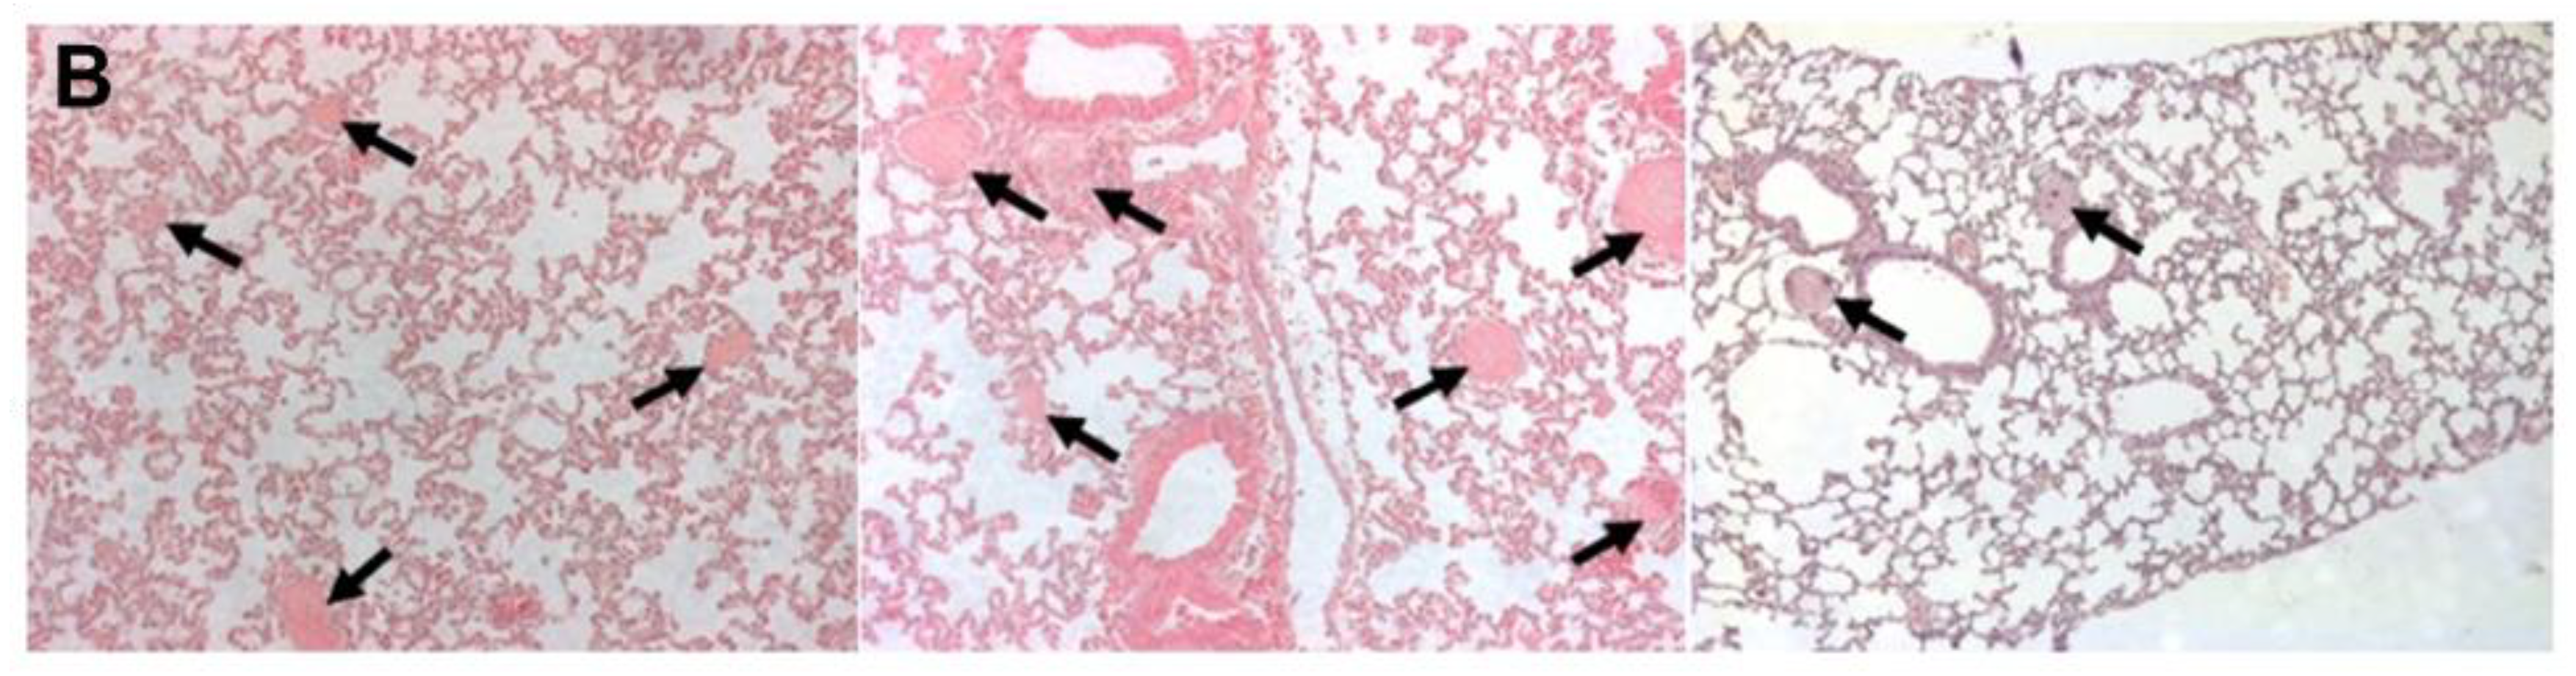

3.2.1. Mouse Studies

3.2.2. Rat Studies

4.3.1. Mouse Data